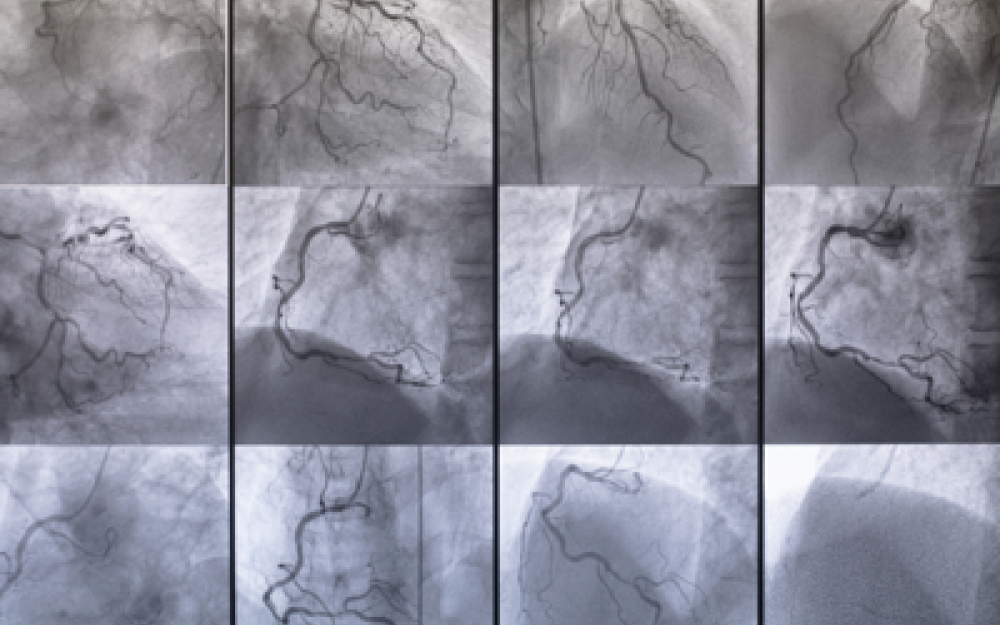

“Ischemie degli arti, aneurismi, ostruzioni carotidee, aterosclerosi, flebo e linfopatie e tumori vascolari sono tra le più importanti cause di mortalità e invalidità nel nostro Paese – spiega Lanza – E sono responsabili del 22% delle morti, subito dopo infarto miocardico (28%) e ictus cerebrale (25%). Oltretutto, le malattie vascolari risultano in costante aumento per l’incremento nella popolazione dell’età media e di diversi fattori di rischio quali ipertensione arteriosa, diabete mellito, dislipidemie, obesità, fumo, inquinamento, comportamenti e stili di vita non corretti, alimentazione errata e inoltre per predisposizioni genetiche”.

“Una peculiarità della malattia arteriosa degli arti inferiori, per esempio, è di rappresentare un importante fattore di rischio per patologie arteriose in altri distretti corporei: i pazienti affetti da arteriopatia periferica hanno un rischio molto elevato di presentare patologia coronarica o carotidea, con un corrispondente aumento del rischio di infarti ed ictus” sottolinea Angelo Santoliquido presidente del Collegio italiano di flebologia (Cif). “Accanto a queste ci sono poi le flebopatie croniche e acute, alcune delle quali responsabili di Embolia Polmonare a rischio di morte improvvisa” aggiunge Roberto Di Mitri, presidente della Società italiana di flebologia.